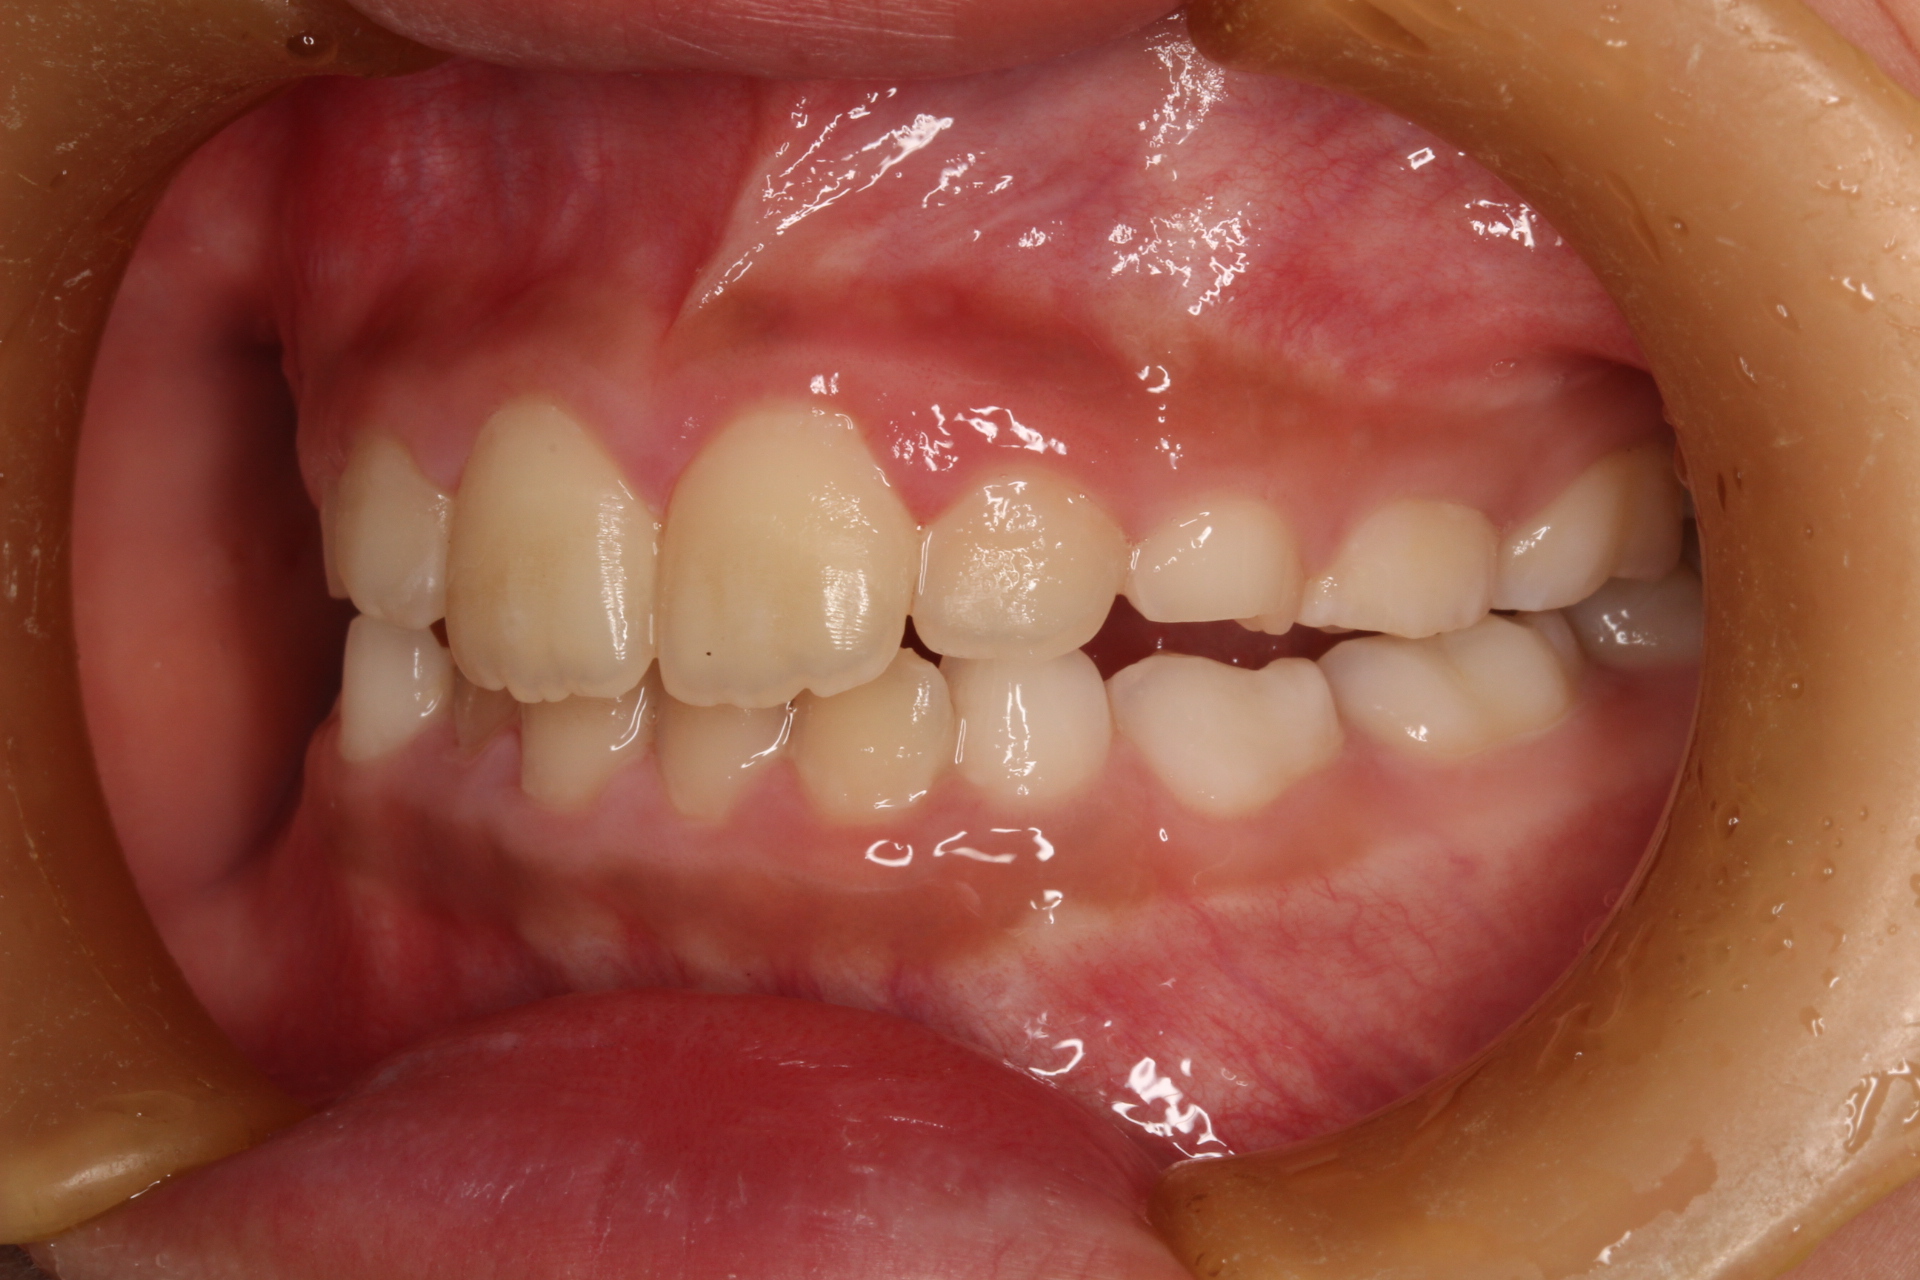

矯正術前:正面

| 主訴 | 下の前歯のがたつきが気になる |

| 治療内容 | 患者様は、下の前歯のがたつきを気にされており、矯正検査後叢生Ⅰ級と診断いたしました |